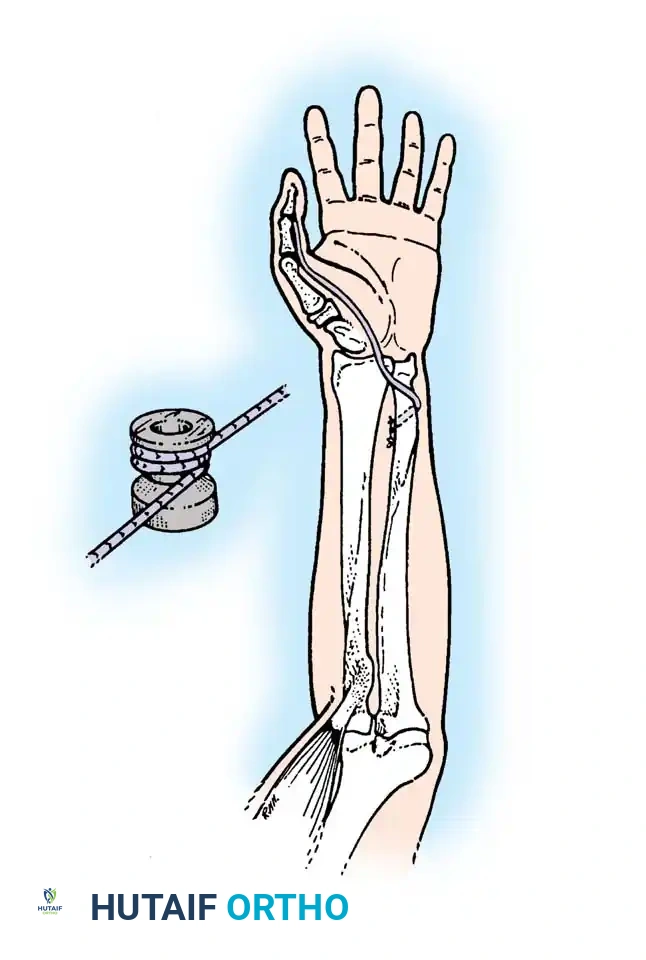

Posterior Deltoid-to-Triceps Transfer (Moberg)

The posterior deltoid-to-triceps transfer, originally described by Moberg, is the gold standard procedure for establishing elbow extension. The posterior deltoid is synergistic with elbow extension and provides excellent excursion and power. Because the deltoid lacks sufficient length to reach the olecranon directly, the procedure requires an intercalated graft (fascia lata, toe extensors, or tibialis anterior tendon).

Lacey et al. reported excellent results using anterior tibial tendon grafts, noting that all patients achieved functional elbow extension and high satisfaction rates. Hentz et al. modified the procedure by utilizing fascia lata or directly attaching the deltoid to the mobilized triceps aponeurosis without a free graft, though this requires extensive mobilization.

Operative Technique: Posterior Deltoid-to-Triceps Transfer (Modified Moberg)

Graft Harvesting and Preparation:

1. Depending on surgeon preference, harvest an appropriate intercalated graft. Moberg originally utilized great toe extensors; however, the anterior tibial tendon or a robust strip of fascia lata is currently preferred due to superior tensile strength.

2. If using fascia lata, harvest a strip approximately 4 cm wide and 15 cm long. Tubularize the graft using a running locking non-absorbable suture.

Tendon Weaving and Fixation:

1. Weave the proximal end of the graft into the mobilized posterior deltoid muscle belly using a Pulvertaft weave technique. Secure it with multiple interrupted horizontal mattress sutures (e.g., 2-0 Ethibond or FiberWire).

2. Expose the distal triceps tendon and olecranon via a separate posterior longitudinal incision.

3. Create a longitudinal split in the triceps aponeurosis.

4. Pass the distal end of the graft subcutaneously from the proximal incision to the distal incision. Ensure the subcutaneous tunnel is wide enough to allow unhindered gliding of the graft.

Setting the Tension (The Critical Step):

1. The tension of the transfer dictates the functional outcome. The goal is to provide maximum extension power without permanently eliminating passive elbow flexion.

2. Adduct the arm and fully extend the elbow. Place the deltoid under maximal physiological tension.

3. Preliminarily suture the graft to the triceps aponeurosis or directly into an olecranon bone tunnel.

4. Test the passive range of motion. You must be able to passively flex the elbow to at least 90 degrees (some authors advocate for full passive flexion, though this risks a lax transfer). If the transfer is too tight, the patient will lose the ability to bring the hand to the mouth.

5. Once optimal tension is confirmed, permanently secure the graft. Place stainless steel surgical markers (clips) at measured distances proximal and distal to the repair site. This allows for radiographic verification of repair integrity postoperatively (Ejeskär technique).